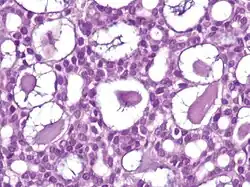

Nodular basal-cell carcinoma (also known as "classic basal-cell carcinoma") accounts for 50% of all BCC.[29] It most commonly occurs on the sun-exposed areas of the head and neck.[30]: 748 [31]: 646 Histopathology shows aggregates of basaloid cells with well-defined borders, showing a peripheral palisading of cells and one or more typical clefts.[29] Such clefts are caused by shrinkage of mucin during tissue fixation and staining.[32] Central necrosis with eosinophilic, granular features may also be present, as well as mucin. The heavy aggregates of mucin determine a cystic structure. Calcification may also be present, especially in long-standing lesions.[29] Mitotic activity is usually not so evident, but a high mitotic rate may be present in more aggressive lesions.[29] Adenoidal BCC can be classified as a variant of NBCC, characterized by basaloid cells with a reticulated configuration extending into the dermis.[29]

| Cystic basal-cell carcinoma | Morphologically characterized by dome-shaped, blue-gray cystic nodules.[31]: 647 |